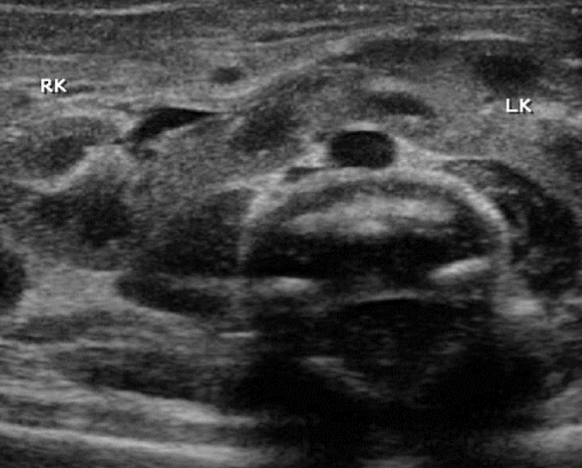

horseshoe kidney

fusion of lower poles, connected via isthmus (anterior to spine and AO)

??